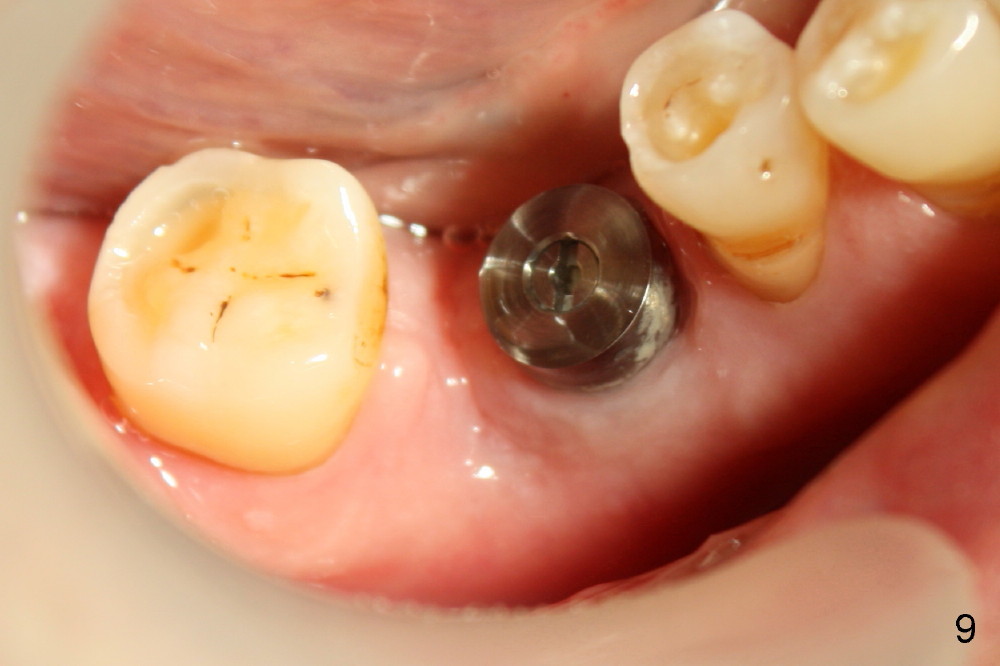

Fig.9 and 10 are taken 1 month 3 weeks postop.